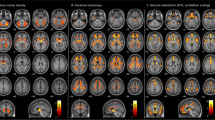

A significant positive correlation was obtained between T2-SNR of putamen and bilateral pre- and postcentral gyrus volume.

To the best of our knowledge, this is the first VBM study to show an age-independent relationship between T2-SNR of putamen and bilateral pre- and postcentral gyrus volumes in healthy adults.